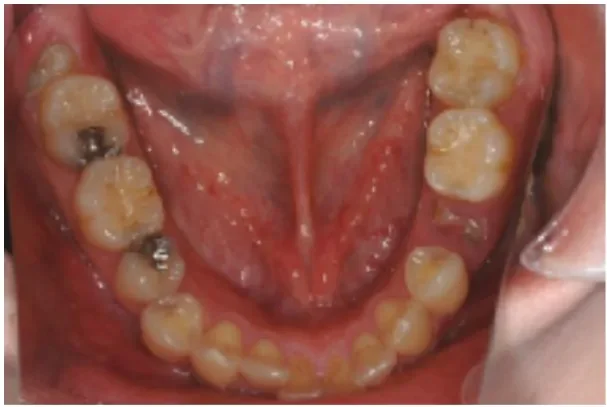

Before

After

虫歯によって欠損してしまった箇所へのインプラント治療

5ヶ月、8回 / 420,000円リスク・副作用:インプラント粘膜炎およびインプラント周囲炎